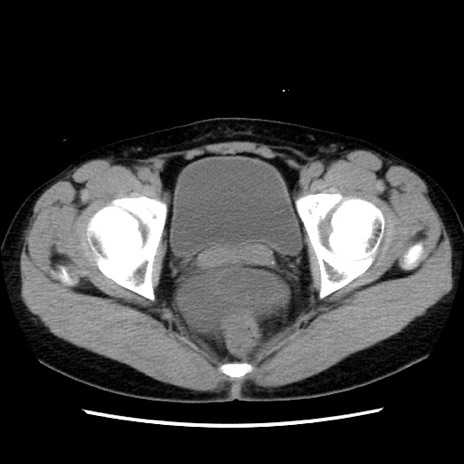

矢状断像